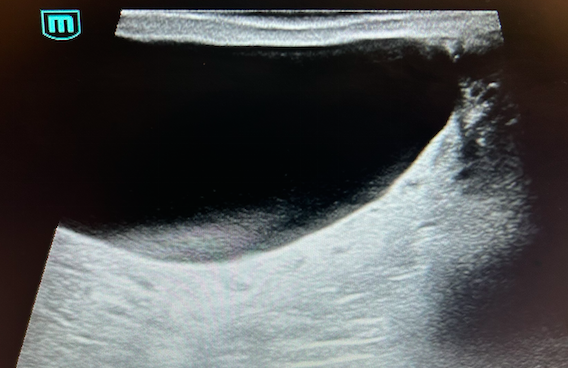

Teste derecho con imagen anecoica de bordes bien definidos y doppler negativo sugerente de quiste en polo superior de 33 x 55 mm. En teste izquierdo imagen anecoica en polo superior de bordes bien definidos y Doppler negativo, de 3 cm de diámetro,sugerente de quiste. Llama la atención adyacente a quiste, imagen en parénquima testicular, de patrón heterogéneo que ocupa el 50% con doppler negativo.